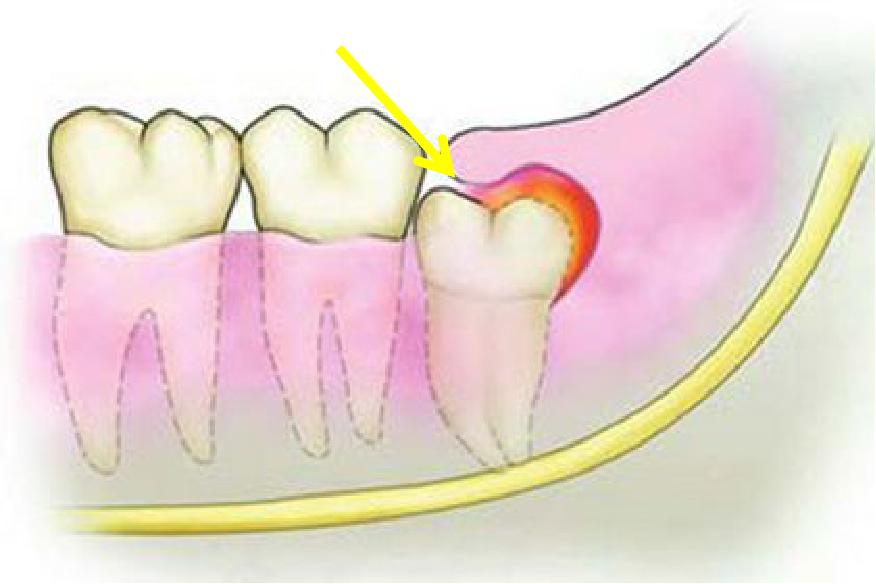

萌出之初,牙冠和牙肉之间形成空隙。上颌因为智齿靠近软腭,刷牙易引起恶心,下颌智齿靠下颌骨的前方,空间有限,牙刷刷头较难深入,清洁不到位,食物残留,细菌聚集,引发感染,称智齿管周炎。

一般无明显全身反应,可表现为牙冠周围肿胀不适,当进食咀嚼、吞咽、开*活口**动时疼痛加重。

2、病情持续发展

局部可出现放射性痛,炎症侵及周围肌肉出现不同程度的张口受限,甚至“牙关紧闭”,伴有面部的局部肿胀。由于疼痛及张口受限,口腔清洁不足,出现口臭、舌苔变厚、患牙龈袋内挤压有咸味分泌物溢出。